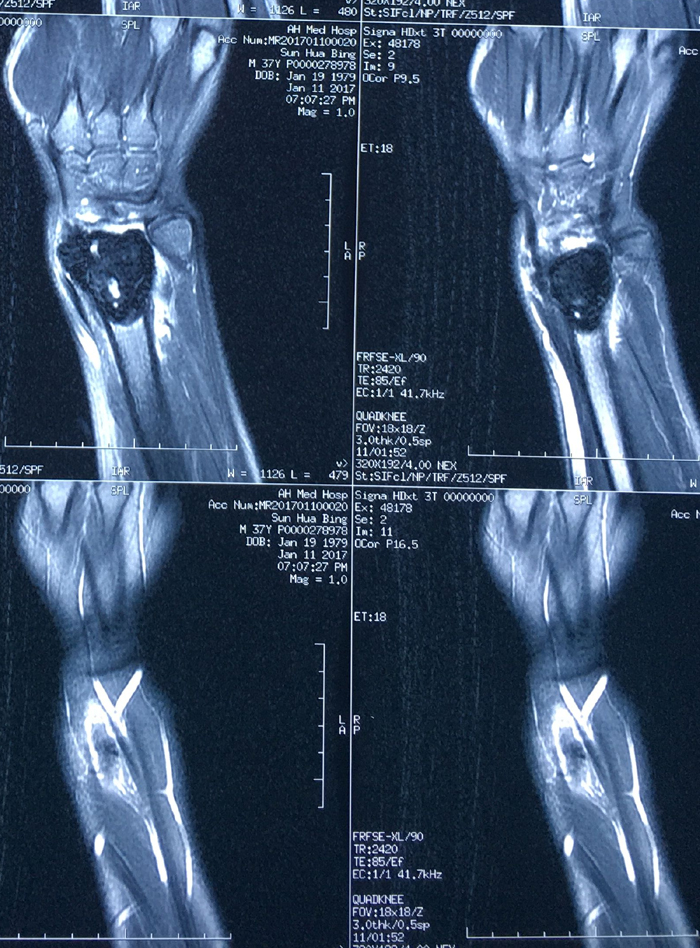

近日,我院关节与骨肿瘤科为一名桡骨远端骨巨细胞瘤Ⅲ级、肿瘤突破间室的男性患者成功实施了肿瘤广泛切除,自体腓骨活骨移植重建桡腕关节术。据悉,对于肢体恶性、侵袭性骨肿瘤,实行广泛外科边界的切除是达到良好的肿瘤学疗效的基础,但这必然会带来肢体结构和功能的更多的丧失。如何既能达到肿瘤的广泛切除,又能最大限度恢复肢体的结构和功能是骨肿瘤外科所追求的目标。肢体结构和功能的生物重建是最接近肢体生理状态的长期有效的重建方式。该方法要求手术者不仅具有精湛的肿瘤外科技术,还要有熟练的显微外科技术,是目前临床上受到普遍推崇的方法。近年来,关节与骨肿瘤科已开展此类手术20多例,取得了良好的效果。